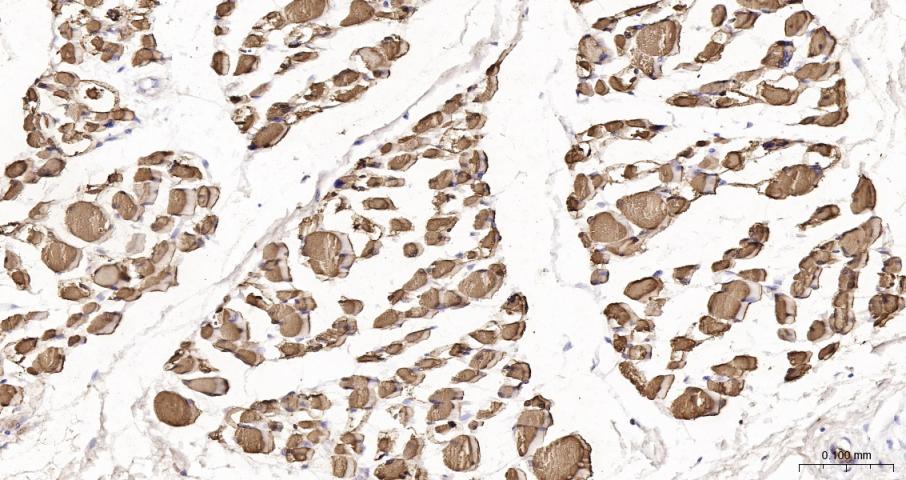

Paraformaldehyde-fixed, paraffin embedded Mouse Heart; Antigen retrieval by boiling in sodium citrate buffer (pH6.0) for 15 min; The section was incubated with Myoglobin Monoclonal Antibody, Unconjugated (bsm-41107R) at 1:200 overnight at 4°C, followed by conjugation to the bs-0295G-HRP and DAB (C-0010) staining.

Paraformaldehyde-fixed, paraffin embedded Rat Heart; Antigen retrieval by boiling in sodium citrate buffer (pH6.0) for 15 min; The section was incubated with Myoglobin Monoclonal Antibody, Unconjugated (bsm-41107R) at 1:200 overnight at 4°C, followed by conjugation to the bs-0295G-HRP and DAB (C-0010) staining.